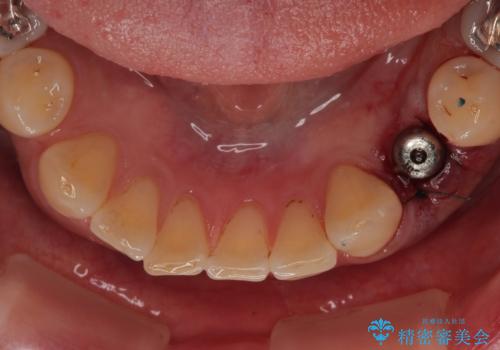

そこで今回は、抜歯と同時にインプラントを埋入する「抜歯即時インプラント治療」をご提案。

外科処置の回数を抑え、治療期間を短縮できる点が大きなメリットです。

治療は計画通りに進み、約3か月で最終補綴まで完了。

見た目だけでなく、しっかり噛める機能も回復し、患者様にも大変ご満足いただけました。